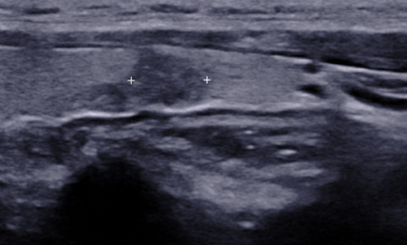

갑상선 고주파 절제술은 1mm 굵기의 얇은 바늘을 이용하여 종양을 치료하는 방법으로, 바늘 끝에서 고주파를 발생시켜 열로 종양을 괴사 시키는 치료법입니다. 사용하는 바늘이 갑상선 종양의 조직검사를 하는 바늘의 굵기와 유사하여 시술 시 환부의 절개가 필요 없으며 시술 후 흉터가 남지 않습니다. 시술 중 국소마취만으로 통증 조절이 가능하며, 시술 후 빠른 일상 복귀가 가능한 치료법입니다.

치료전

치료후